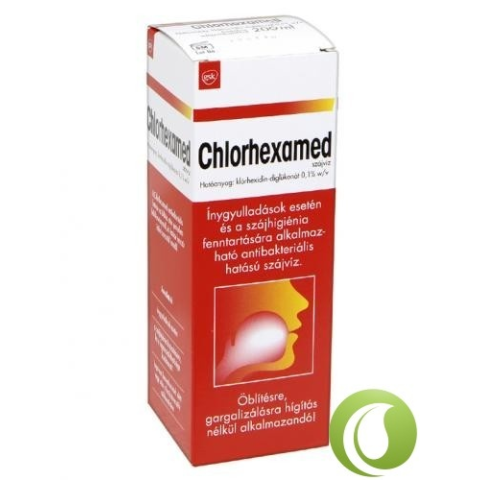

Chlorhexamed Antibakteriális Szájöblítő 200 ml

A Chlorhexamed szájöblitő a szájüreg és a garat gyulladásainál alkalmazható széles spektrumú antiszeptikum. Javasolt a szájüreg és a garat gyulladásaira, szájhigénia biztosítására, fogorvosi beavatkozás elött és után. Használat: Naponta 2x a mellékel